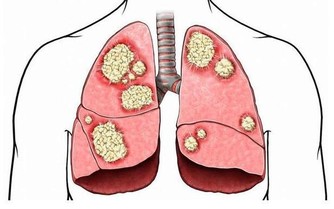

這是心血管疾病或肺部腫瘤的指標。